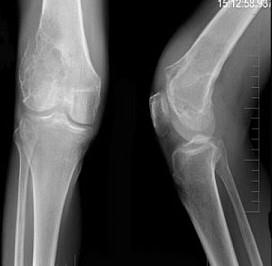

问题 30岁男性患者,右膝关节酸胀,疼痛不适5个月,X线检查如图所示,下列诊断最为合适的是 ( )

选项 A、动脉瘤样骨囊肿 B、Ewing肉瘤 C、骨囊肿 D、骨血管瘤 E、骨巨细胞瘤

答案 E